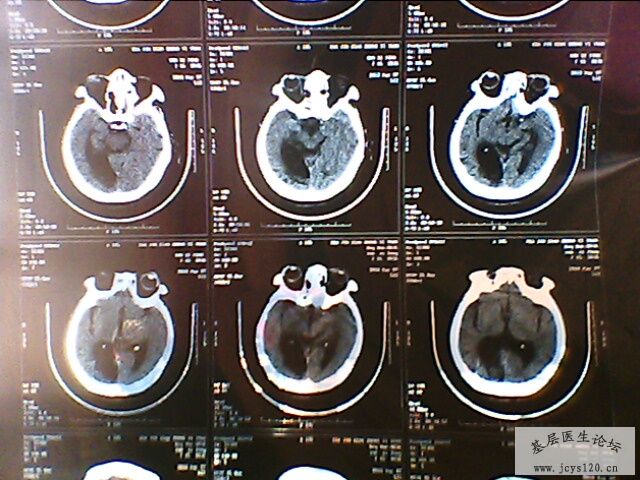

右侧肢体活动障碍半小时

患者,女,65岁,在半夜起来上厕所时发现右侧肢体不能活动,无头痛,无恶心呕吐,无意识障碍,无大小便失禁,持续大概十分钟后症状消失,唯感觉右侧肢体稍无力,为进一步检查和治疗来诊。

查体:血压160/90 mmHg 心率80次/分

自主体位,神志清楚,语言流利,双侧瞳孔等大等圆,对光反射灵敏,伸舌居中,心肺听诊、腹部检查无异常,四肢活动正常,肌力正常,病理征未引出,生理反射存在。

既往史:既往体健,三天前在家因为头晕测血压200/100mmHg ,在家口服药物(复方利血平)后血压降至正常。无心脑血管疾病病史。